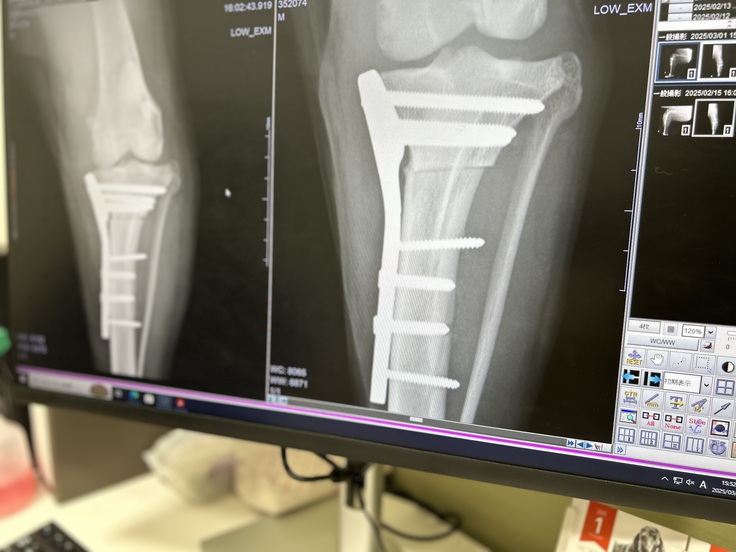

抜糸とレントゲン

抜糸完了、レントゲンチェック。

骨のつながり具合は順調そのものだった。先生も歳の割には回復が早いと言ってくれた。脚が痩せ細っていることも確認したが、半年くらいでだいぶ戻るみたいだ。

しかし、ただの抜糸とレントゲンでも万単位の費用が普通にかかる。今のところ、総額では100万行くか行かないかだ。TPLO手術にかかる総額は今後この怪我を負われた飼い主のためにも公明正大に公開しよう。